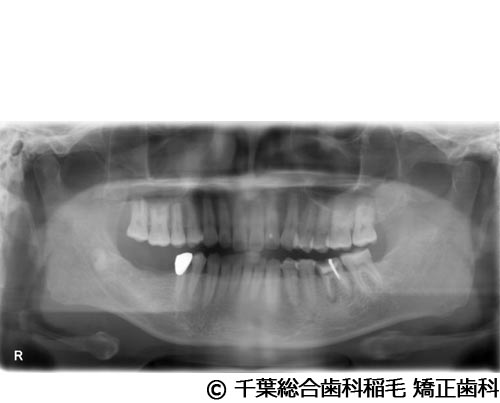

【症例1】下顎大臼歯3本インプラント埋入手術

- 治療前

- 治療後

- 治療名

- 下顎大臼歯3本インプラント埋入手術

- 費用

- 1,400,000円(税込)

- 期間

- 10ヵ月

治療内容

-

患者様の症状

左下第一大臼歯は他院で治療中でしたが、治療がなかなか進まず、他の部位にもお痛みが続いていたため、当院にご相談に来られました。

治療法

左下第一大臼歯は保存が厳しい状態だったため、抜歯となりました。

ご来院時から欠損状態だった右下第一、第二大臼歯も含め、欠損補綴についてお話させていただき、インプラントでの治療を選択されました。 -

治療結果

お痛みも和らぎ、現在も定期検診で拝見させていただいています。

※治療結果は患者様によって個人差があります。